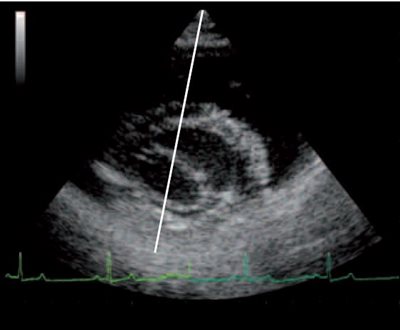

photo 1

Coupe petit axe transventriculaire par abord droit mode bidimensionnel : positionnement de la ligne de tir Temps Mouvement (TM) perpendiculaire aux structures cardiaques choisies (parois et cavités ventriculaires).

À partir d’une coupe standard bidimensionnelle, un axe de tir TM (ligne de tir) est choisit et positionné perpendiculairement aux structures étudiées (PHOTO 1).